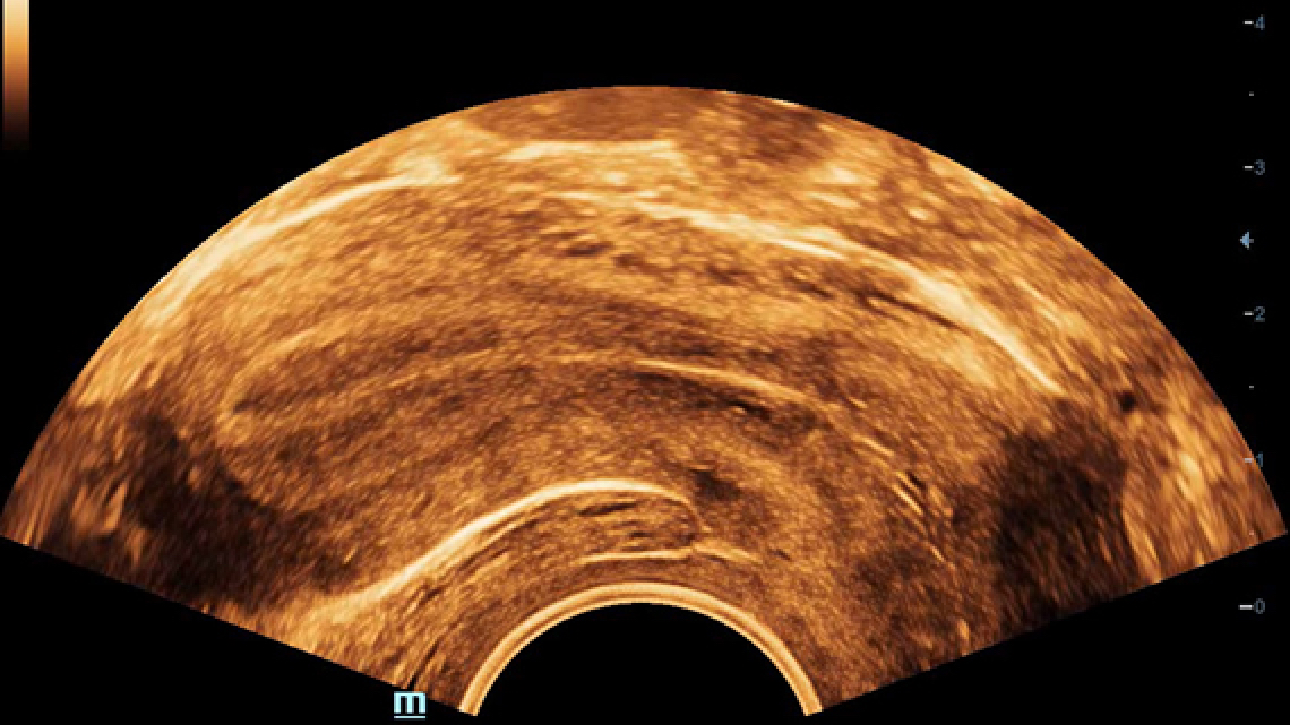

DC-70 Exp

–Ю–±–Ј–Њ—А

X-Insight вАУ —Н—В–Њ –Њ—В–ї–Є—З–љ–Њ–µ —А–µ—И–µ–љ–Є–µ –і–ї—П –Њ–њ—А–µ–і–µ–ї–µ–љ–Є—П –љ–Њ–≤—Л—Е –≤–Њ–Ј–Љ–Њ–ґ–љ–Њ—Б—В–µ–є.

–°–Њ–≤–Љ–µ—Б—В–љ–Њ —Б —Б–Њ–≤—А–µ–Љ–µ–љ–љ—Л–Љ–Є —Г–ї—М—В—А–∞–Ј–≤—Г–Ї–Њ–≤—Л–Љ–Є —В–µ—Е–љ–Њ–ї–Њ–≥–Є—П–Љ–Є –љ–Њ–≤–Њ–µ —А–µ—И–µ–љ–Є–µ –Њ—В Mindray –њ—А–µ–Њ–±—А–∞–Ј—Г–µ—В –∞–Ї—В—Г–∞–ї—М–љ—Л–µ –Ј–∞–і–∞—З–Є –Ї–ї–Є–µ–љ—В–Њ–≤ –≤ –Ї–ї–Є–љ–Є—З–µ—Б–Ї–Є–µ –њ–Њ—В—А–µ–±–љ–Њ—Б—В–Є.

–°–Є—Б—В–µ–Љ–∞ DC-70 Exp —Б X-Insight –њ–Њ–Љ–Њ–≥–∞–µ—В —Г–њ—А–∞–≤–ї—П—В—М –њ–Њ–≤—Б–µ–і–љ–µ–≤–љ–Њ–є –Ї–ї–Є–љ–Є—З–µ—Б–Ї–Њ–є –њ—А–∞–Ї—В–Є–Ї–Њ–є —Б –ї–µ–≥–Ї–Њ—Б—В—М—О –Є —Г–≤–µ—А–µ–љ–љ–Њ—Б—В—М—О.

–Ю—Б–љ–Њ–≤—Л–≤–∞—П—Б—М –љ–∞ –≥–ї—Г–±–Њ–Ї–Њ–Љ –њ–Њ–љ–Є–Љ–∞–љ–Є–Є –њ–Њ—В—А–µ–±–љ–Њ—Б—В–µ–є –Ї–ї–Є–µ–љ—В–Њ–≤, –Ї–Њ–Љ–њ–∞–љ–Є—П Mindray —А–∞–Ј—А–∞–±–Њ—В–∞–ї–∞ —Б–Є—Б—В–µ–Љ—Г DC-70 Exp —Б X-Insight, —З—В–Њ–±—Л –Њ–±–µ—Б–њ–µ—З–Є—В—М eXpress Clarity, eXceptional Intelligence, eXceeding Experience.